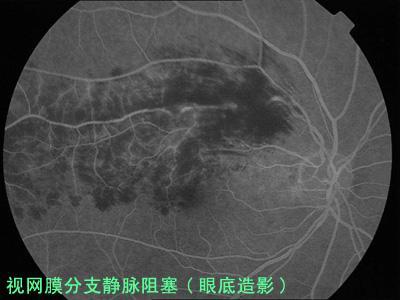

2.1 眼底荧光血管造影(FFA) 主要用于了解阻塞的程度,黄斑区是否有渗漏,视网膜无灌注区的范围,以及有无新生血管形成等情况,对诊断、治疗和判断该病的预后期有重要作用。

3.2 视网膜分支静脉阻塞 以颞上支阻塞最多见。主要表现为视力不同程度下降。周围视野多无影响,而中央视野则可出现中心暗点。眼底检查可见象限性视网膜浅层出血、视网膜水肿,可有棉絮状斑形成。